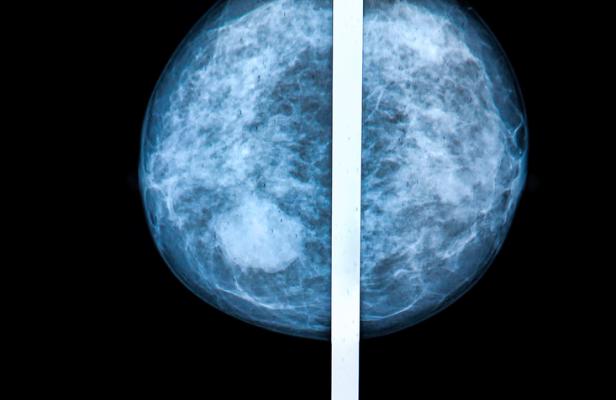

March 30, 2022 — Breast density notifications aim to educate women about the risks of high breast density, defined as having more fibroglandular tissue than fatty tissue, as visualized on a mammogram. Prompted by activists whose own breast density had obscured breast cancers on their mammograms, 38 U.S. states and Washington, DC, have enacted legislation requiring written notification of a patient’s breast density (DBN) after a mammogram and language for a federal notification is forthcoming from the U.S.A. Food and Drug Administration.